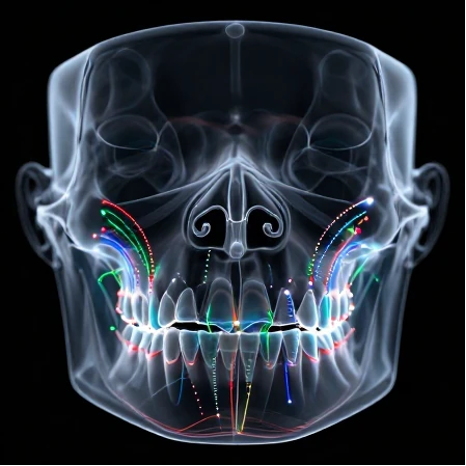

Practical Application of Skeletal Anchorage (TADs): Moving beyond mere placement, we teach precise insertion techniques in the clinical setting (using 3D-printed guides) and how to design Three-Piece Force Systems for simultaneous Sagittal, Vertical, and Torque control. Emphasis on post-insertion radiographic protocols for confirming TAD positioning.

Digital Technology as a Clinical Ally: Integrating CBCT data for routine assessment of bone density and proximity to critical structures, directly aiding in the optimal selection of anchorage sites. Practice sessions utilizing industry-standard software for Virtual Treatment Planning (VTO) optimization based on patient-specific data.

Risk Management and Periodontal Health Preservation: Training in Low-Force Delivery protocols specifically in areas of thin bone anatomy (e.g., posterior molars). Introduction to Acceptable Clinical Risk Criteria (ACRC) for root resorption and immediate therapeutic interventions (such as the application of Bioactive Agents at the root surface) should complications arise.

Corticotomy/Piezo-Assisted Treatments: Instruction on Surgical Guides derived from CBCT for partner surgeons, and understanding how to apply forces immediately post-procedure to maximize effect.